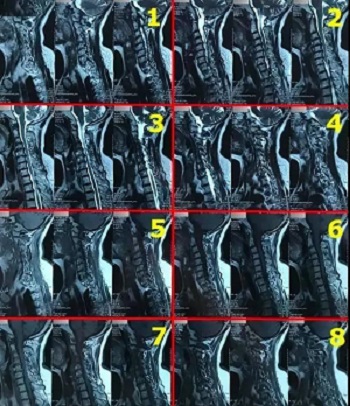

九、翻拍磁共振图像时,因为磁共振片子很大,而且一张片子上有很多图像(如下图),所以,单纯的拍一张片子,因为手机拍摄,像素以及翻拍质量不好,且放大后图像会发虚,细节看不清楚,所以,基本上是没用的,对于医生阅片来说,质量太差,不能获取图片上的有效信息。

十、因此需要将磁共振的一张片子,进行分区域局部放大拍摄,尽可能的将片子上的细节拍摄清楚,将一张磁共振片子进行分区。

十一、将分区的磁共振图像,按顺序进行拍摄,即可获取如下比较有价值的清晰图片

(区域1)

(区域2)

(区域3)

(区域4)

(区域5)

(区域6)

(区域7)

(区域8)